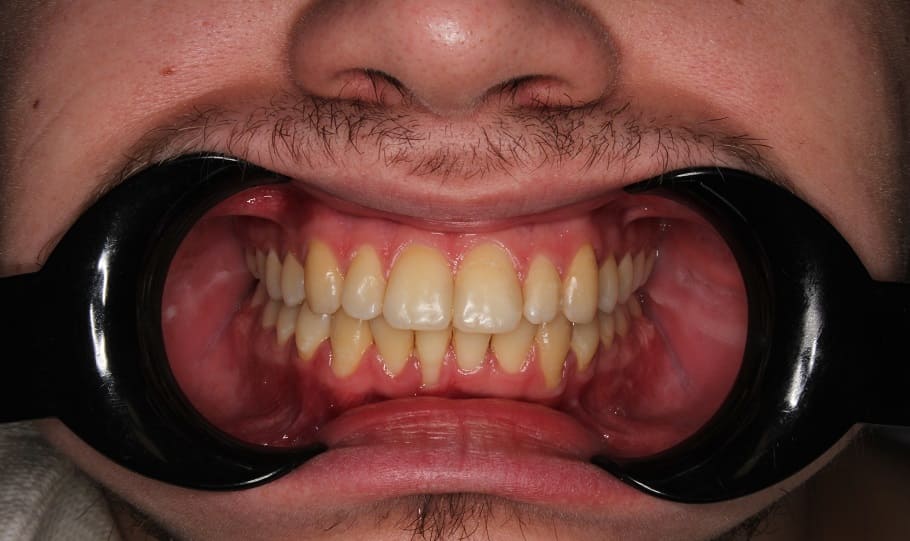

Лечение на самолигирующей брекет-системе Н4. Ортодонтическое лечение заняло 2 года.